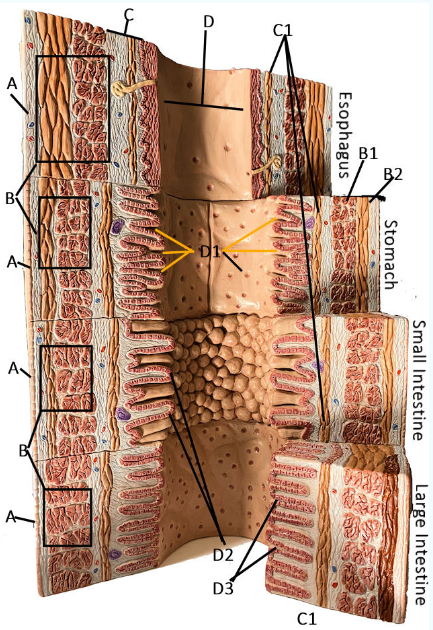

A

Serosa

B Esophagus

Muscularis externa: skeletal, skeletal/smooth, and smooth, circular and longitudinal

B Stomach

Oblique, circular, and longitudinal smooth muscle

B Small intestine

circular and longitudinal smooth muscle

B large intestine

circular and longitudinal smooth muscle

C

Submucosa: areolar and dense connective tissue

D

Lumen

D1

Gastric glands/pits

D2

Villi of small intestine

D3

Intestinal crypts of large intestine